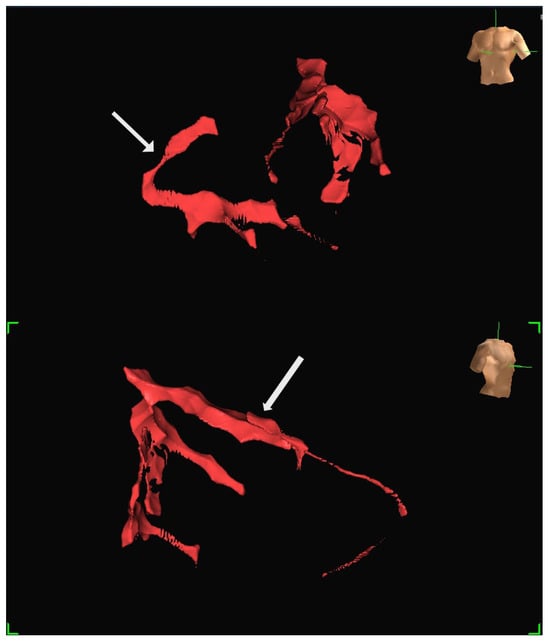

A human feasibility study involving multiple participants was conducted using the EnSite Precision system [13]. Insulated Sion Blue coronary guidewires (Asahi Intec, Japan) were tracked through epicardial arteries, including the left anterior descending and right coronary arteries, to produce anatomical reconstructions closely matching conventional angiographic images. The mapping system tracked the distal wire tip based on impedance field localisation. System accuracy was further evaluated in a custom-built water bath model incorporating segmented CT data. In this controlled setup, bipolar catheters fabricated from over-the-wire balloons and coronary wires were advanced through fixed vessel phantoms, confirming consistent localisation and map generation. Representative three-dimensional reconstructions generated using the EnSite Precision mapping system are shown in Figure 4 and Figure 5. These panels depict different views from the same patient, illustrating how coronary anatomy was mapped and visualised during the feasibility study.

Figure 5. Additional views of the same patient dataset shown in Figure 4, demonstrating the ability to visualise the vessel course from different angles: (Top) The LAD is marked by an arrow. (Bottom) RCA is marked by an arrow. Both images are displayed in LAO projection at different angulations.